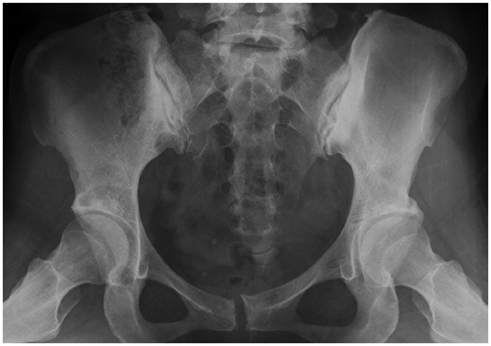

Systematic Approach of Sclerotic Bone Lesions Basis on Imaging Findings

- Sclerotic bone lesions are common, but there are diverse groups of tumors and non-tumorous lesions. Although plain radiograph and computed tomography can reveal important characteristics of these lesions, diagnosis is often challenging for radiologists. A systematic approach and familiarity with the imaging features of various sclerotic bone lesions may be greatly helpful for eliminating in the differential diagnosis. This review describes the systematic approach to diagnosing sclerotic bone lesions based on imaging findings.